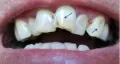

Здравствуйте доктор, у меня такая проблема — стерлась эмаль на зубах. Не на всех, слава богу — на двух передних. На одном у самой десны, а на втором, примерно на пол зуба. Пробовала разные пасты — не особо помогают. В нашем городке стоматологи работают еще советскими методами и ничего толком кроме пломбы предложить не могут.

Здравствуйте, Екатерина. К сожалению, без очного осмотра я не смогу точно поставить диагноз. Есть разные причины подобных нарушений состояния зубной эмали. Возможно это эрозия, а возможно и клиновидный дефект. В каждом случае назначается разное лечение. Ведь стерлась эмаль на зубах не просто от времени и это далеко не обычная косметическая проблема. Нередко требуется дополнительно проконсультироваться у ортодонта, ортопеда и эндокринолога.

Если же говорить об общих рекомендациях, то чаще всего, чтобы нивелировать последствия стершейся зубной эмали и избавить пациента от неприятных ощущений, используется «бондинг». Этот наиболее недорогой и быстрый метод лечения. Также можно установить виниры. Но это уже более дорогой вариант, который имеет ряд недостатков.